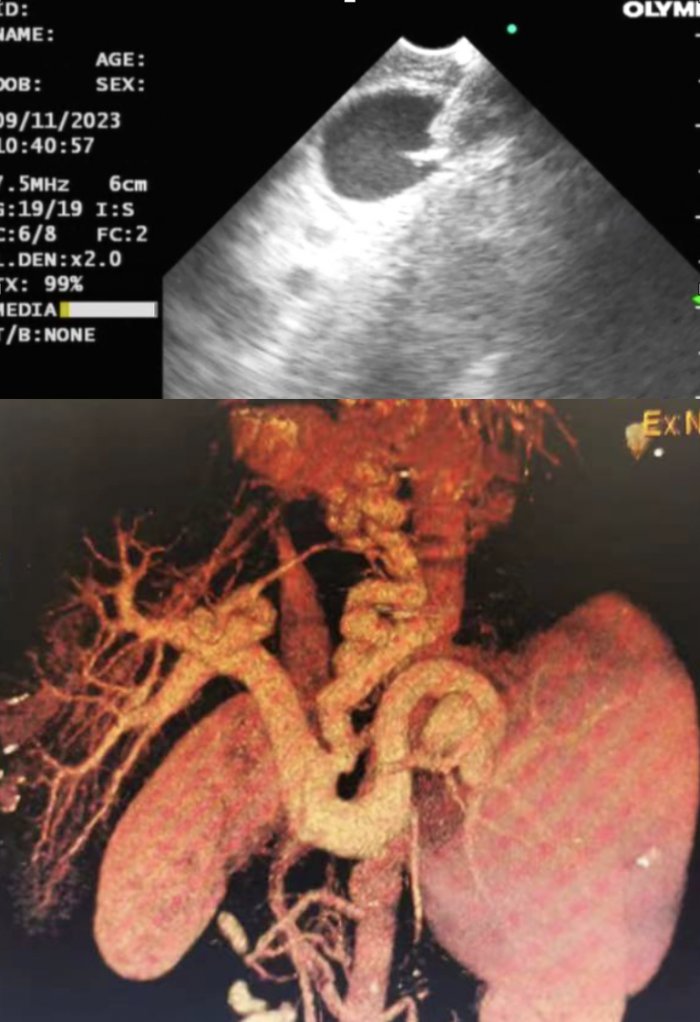

内镜中心擅长消化道出血治疗,尤其是食管胃静脉曲张的内镜治疗处国内领先水平,每年抢救消化道出血急危重病人千余例。李坪主任首创内镜下精准食管胃静脉曲张断流术(ESVD),使得广大食管胃静脉曲张患者从中获益。近年来ESVD技术联合金属夹及LOOP技术,实现了对合并自发性门体分流静脉曲张患者的微创内镜治疗,填补了国内外空缺。基于上述工作基础已获得发明专利2项,在全国各地100多家医院进行技术推广应用,培养进修医师数百人。编写专著两部《食管胃静脉曲张探索》和《内镜下精准食管胃静脉曲张断流术(ESVD)》,形成教学相长的特色医疗体系。2023年底,消化内科进一步发展超声内镜引导下食管胃静脉曲张治疗(EUS-SVD),取得更好疗效。

(超声内镜引导下食管胃静脉曲张组织胶栓塞治疗)